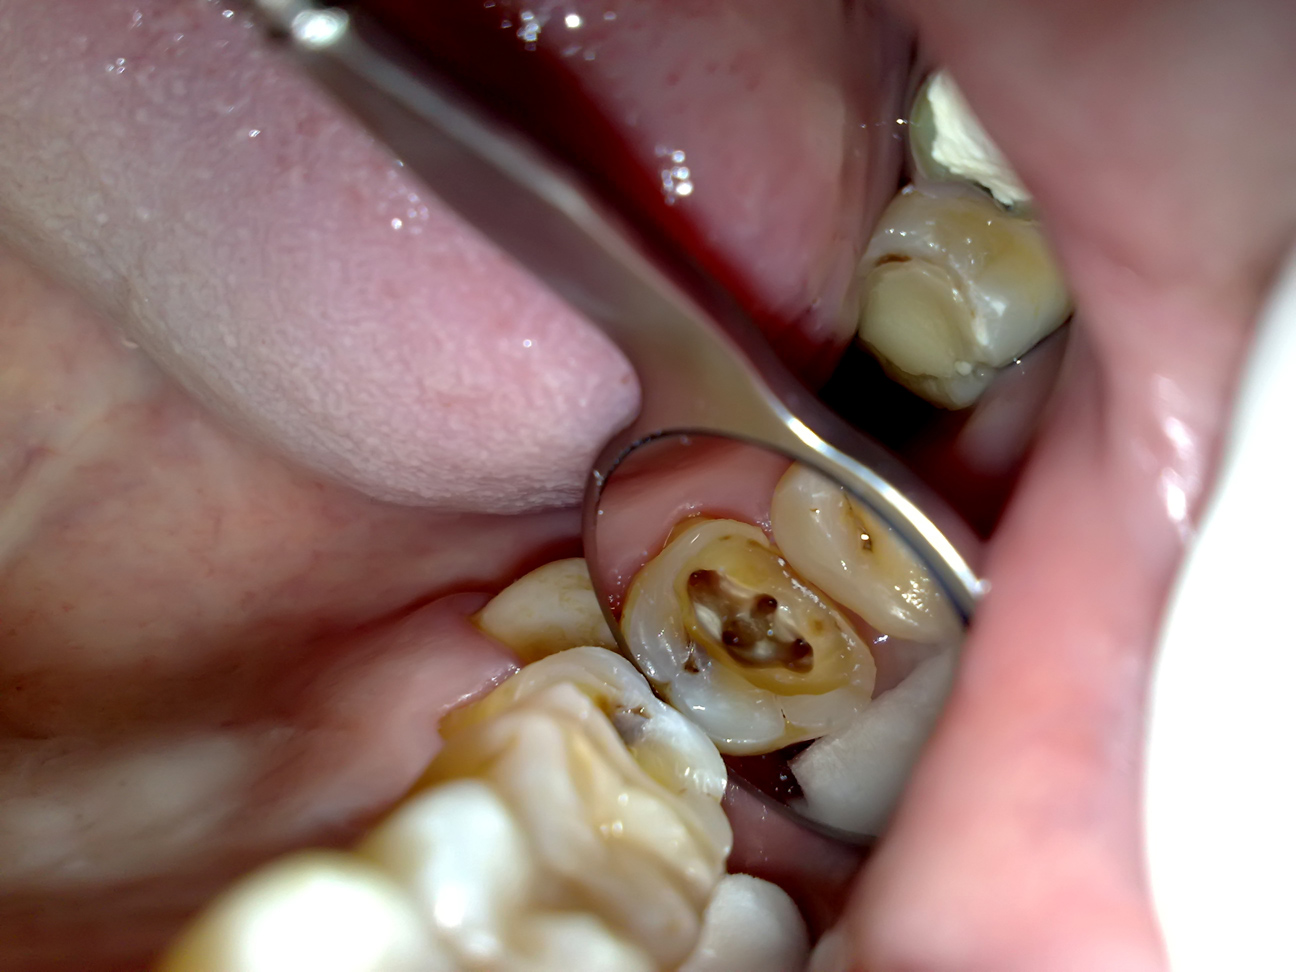

- Gigi merupakan salahsatu organ penting untuk meghaluskan masakan yang kemudian dicerna oleh pencernaan. Gigi juga bahwasanya memiliki pelindung biar tidak terjadi kerusakan pada gigi, disebut juga email gigi. Namun, jikalau kebiasaan mengkonsumsi cantik terlalu hiperbola dan tindakan menyerupai menggosok gigi dengan teratur diabaikan maka tetap saja gigi sanggup berlubang. Makara untuk penggemar masakan serba cantik harus hati-hati. Makanan cantik yang biasanya banyak digemari dan sanggup merusak gigi yakni cokelat, camilan cantik manis, permen dan masih banyak makanan-makanan cantik lainnya.

- Masalah sakit gigi yang menimpa seseorang biasanya dikarenakan gigi berlubang. Meskipun demikian, kerusakan gigi tentu saja sanggup dicegah dengan melaksanakan kebiasaan sehat untuk merawat gigi, yaitu menggosok gigi setelah makan dan sebelum tidur. Mengurangi masakan yang sanggup menjadikan kerusakan gigi, dan memakai produk yang sanggup mencegah dari kerusakan gigi.